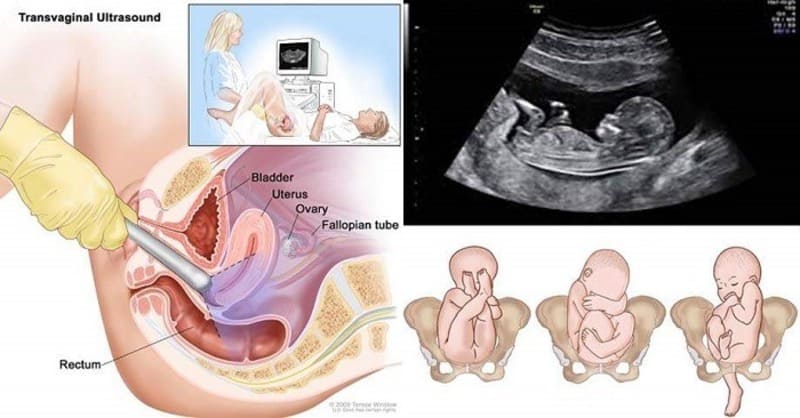

Siêu âm thai đầu dò là phương pháp siêu âm sử dụng đầu dò chuyên dụng đưa vào âm đạo để quan sát rõ hơn tử cung, buồng trứng và thai nhi trong giai đoạn sớm của thai kỳ. Kỹ thuật này cho hình ảnh sắc nét hơn so với siêu âm bụng, đặc biệt hiệu quả trong 3 tháng đầu. Bác sĩ có thể phát hiện vị trí làm tổ của phôi, tình trạng túi thai, tim thai và các bất thường sớm. Thủ thuật diễn ra nhẹ nhàng, không gây đau đớn và an toàn cho mẹ và bé. Siêu âm đầu dò thường được chỉ định khi cần đánh giá chính xác tuổi thai hoặc nghi ngờ thai ngoài tử cung.

Siêu âm thai đầu dò được thực hiện để giúp bác sĩ quan sát chi tiết hơn tình trạng của thai và cơ quan sinh sản trong giai đoạn sớm. Phương pháp này hỗ trợ phát hiện các bất thường và đánh giá sự phát triển của thai nhi một cách chính xác. Các mục đích chính của siêu âm thai đầu dò:

• Xác định vị trí túi thai: Giúp kiểm tra xem phôi đã làm tổ đúng trong buồng tử cung hay có nguy cơ thai ngoài tử cung.

• Kiểm tra tim thai và sự phát triển ban đầu: Phát hiện tim thai và các dấu hiệu sống của phôi từ rất sớm, thường từ tuần thứ 5-6.

• Đánh giá tình trạng tử cung và buồng trứng: Phát hiện các bất thường như u xơ, nang buồng trứng hoặc vấn đề ở niêm mạc tử cung.